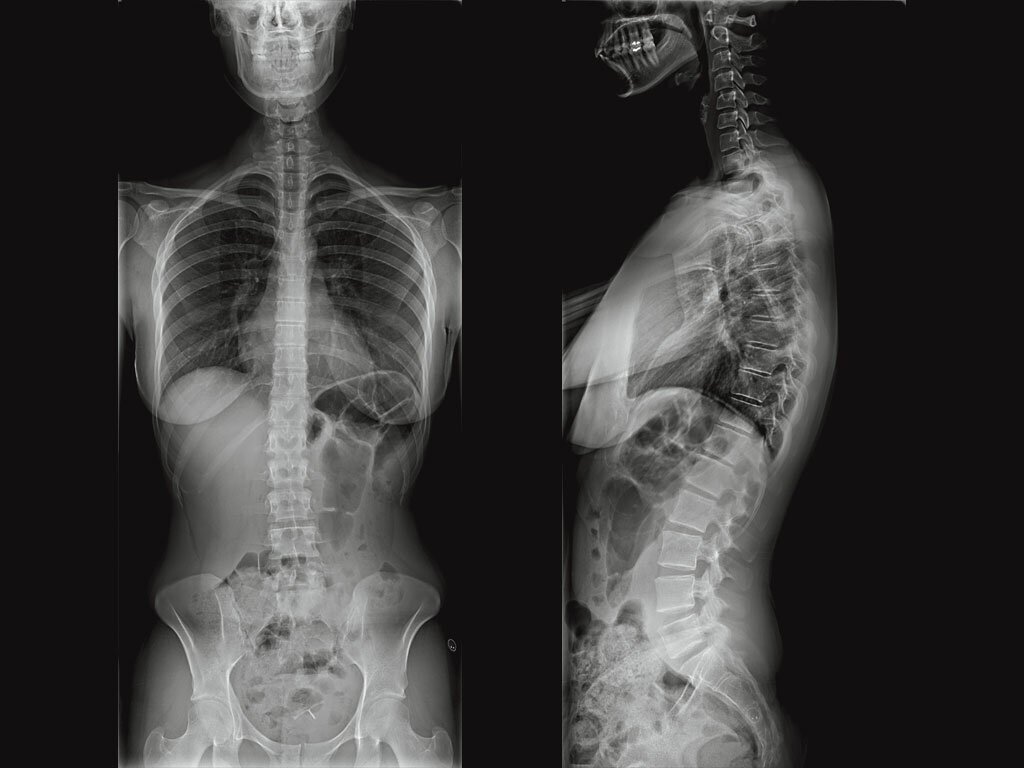

Рентгеновские снимки плат в высоком разрешении

Раздел: Точки зрения